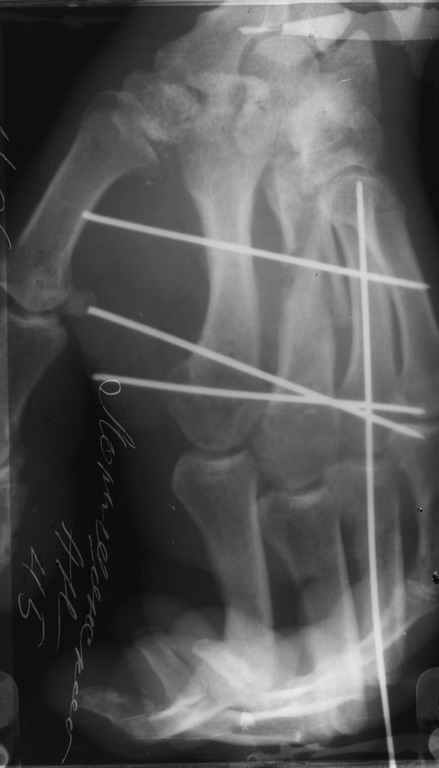

Диагноз: Стойкая Смешанная дермотеногенная контрактура 3,4 пальца правой кисти.

Судя по выписному эпикризу, рентгенограммам и фотографиям, пациенту

показано этапное лечение.